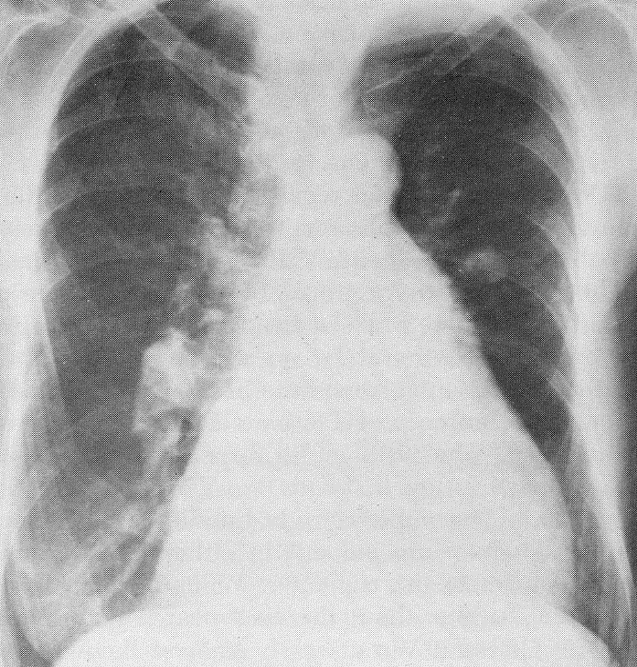

Left untreated, this patient developed severe pulmonary hypertension and reversal of the intracardiac shunt from left to right to right to left (Eisenmenger syndrome). The findings on her chest x-ray are characteristic of chronic pulmonary hypertension with marked enlargement of the main pulmonary artery segment and right ventricle (RVH) (note the rounded apical segment and the encroachment of the ventricle on the retrosternal space).

On physical examination, RVH is suspected whenever the right heart border extends beyond 4 cm from the midsternal line in the right 4th intercostal space, particularly when accompanied by retrosternal dullness and a left parasternal tap or thrust. As was true in the presented case, patients with Eisenmenger syndrome may show a lip color that is both cyanotic and plethoric, a result of hypoxemia and secondary polycythemia, respectively.